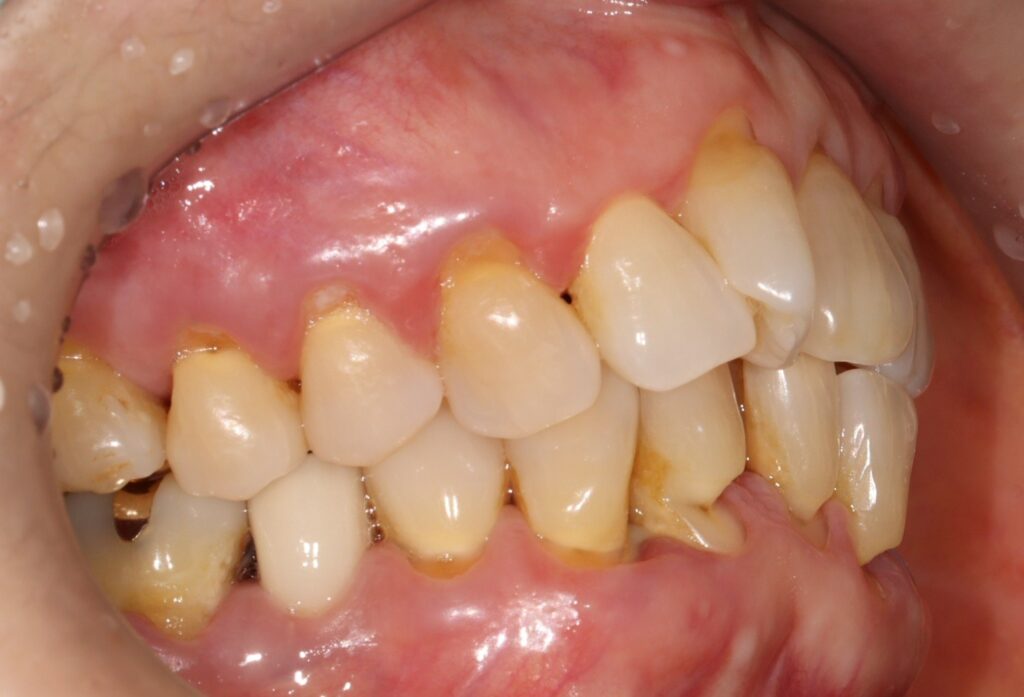

오늘 소개해 드릴 내용은 심하게 패인

치경부를 레진으로 수복하신 것을

사진을 보며 설명해 드리려고 합니다.

환자분께서는 70대 여성분으로

치아의 신경이 노출될 정도로 심하게

치경부가 패여 있는 상황이었는데요.

치아 목 부위가 U자형 또는 V자형으로 패인 형태를

보이며 칫솔질 시 통증과 치아 색 변화가 동반됩니다.

심한 경우에는 치아 신경(치수)까지 노출돼

일상생활이 불가능할 정도의 통증을 호소하기도 합니다.